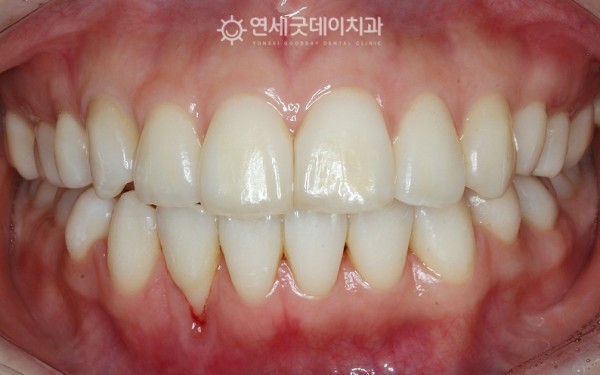

잇몸퇴축을 주소로 내원해주신 30대 여성 환자분이십니다.

환자분은 오래 전 교정했던 치과가 폐업하면서

교정 유지관리가 미흡해지고

이러한 이유로 치근 위치가 이동하여

잇몸 밖으로 돌출되어 있는 상태였습니다.

아랫니 부분교정으로

치아배열을 개선하는 과정을 거쳤고

치아가 잇몸뼈 안으로 올바르게 위치하면서

치근 주변으로 잇몸이 점차 차오르는 게 관찰되었습니다.

약 10개월 간의 치주교정이 종결되었으며,

단순한 심미 개선 뿐만이 아니라

치아와 잇몸의 기능적 안정성이 확보되었습니다.

※ 치료전후 촬영시기

(전) 2024년 10월 (후) 2025년 8월